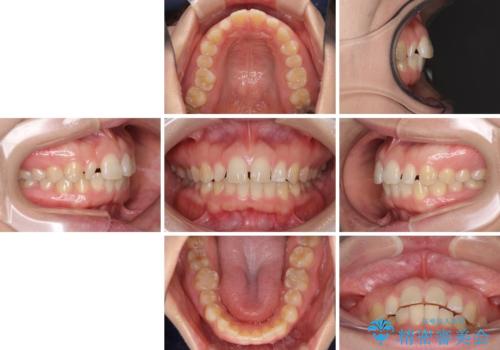

- 前歯の空隙と矮小歯を気にして来院された患者様です。

上下の歯列不正はインビザラインにより整えることとしました。

矯正治療の後に、前歯1歯と奥歯をオールセラミックにて治療することとしました。

矯正治療により矮小歯前後にスペースを作りながら歯列を整え、セラミッククラウン装着後に最終的に歯列と咬合を仕上げました。